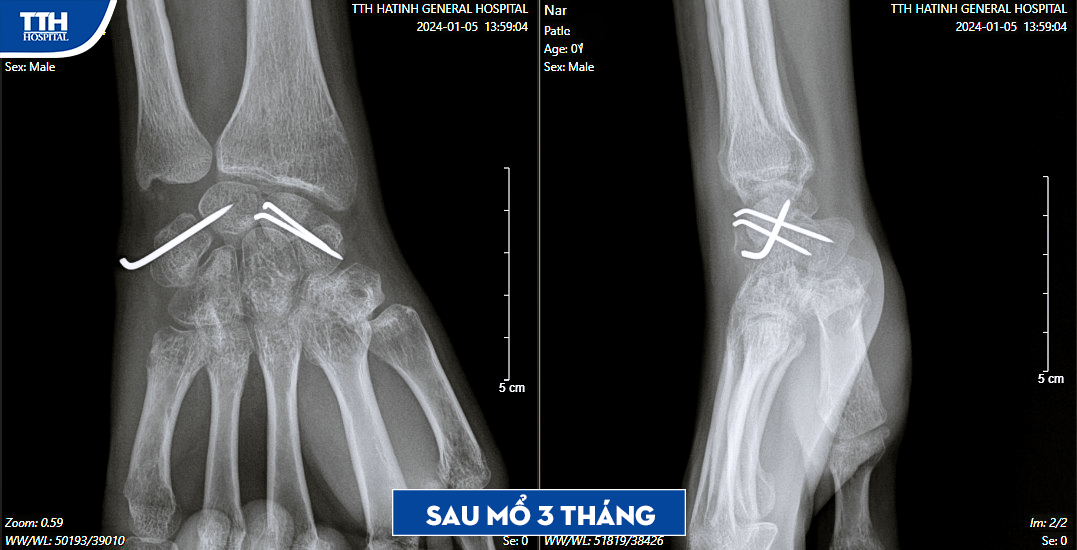

Tại Bệnh viện Đa khoa TTH Hà Tĩnh, qua thăm khám và làm các xét nghiệm cận lâm sàng, bệnh nhân được chẩn đoán bị gãy xương thuyền - trật xương nguyệt cổ tay phải bỏ sót. Đây là một tổn thương nặng nề và được phát hiện muộn. Sau đó, bệnh nhân được phẫu thuật nắn trật khớp, tái tạo dây chằng, ghép xương có cuống mạch vào ổ gãy xương thuyền và xuyên đinh cố định xương.

Hiện tại, sau mổ 3 tháng, xương lành tốt, hết đau, bệnh nhân được tháo phương tiện cố định xương và tập luyện theo hướng dẫn. Ths.BS Đậu Đức Thảo - Khoa Chấn thương Y học thể thao, Bệnh viện Đa khoa TTH Hà Tĩnh là người trực tiếp thực hiện ca phẫu thuật khuyến cáo: “Bệnh nhân sau khi chấn thương vùng cổ tay nên sơ cứu đúng cách (chườm lạnh, băng ép, bất động, kê cao tay) và khám sớm tại cơ sở y tế uy tín để được chẩn đoán và điều trị, tránh những biến chứng xấu và giảm chức năng cổ tay.”